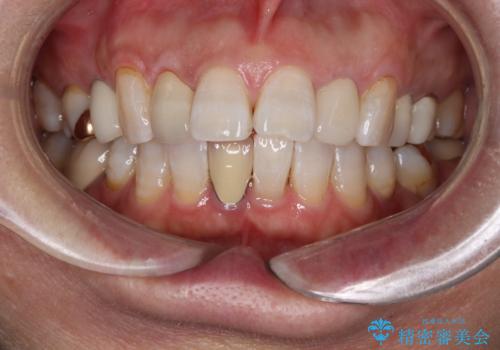

- 矯正歯科治療

- 2012~2025年6月

- 000件

- インビザライン

- 2015~2025年6月

最新の症例

Latest cases